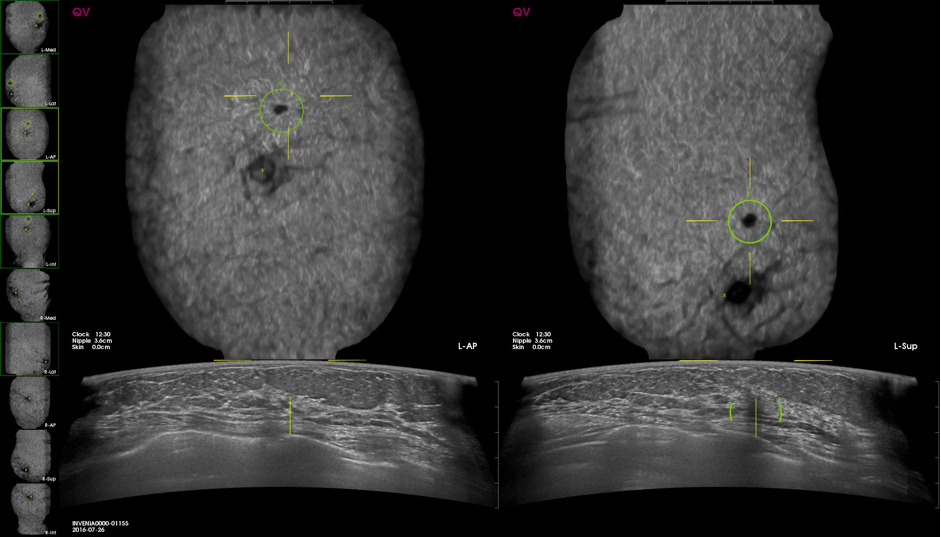

Το σύστημα CAD, αφού επεξεργαστεί τα δεδομένα από τις εικόνες του αυτοματοποιημένου υπερηχογραφήματος (ABUS), μέσω ειδικού αλγορίθμου επισημαίνει δυνητικά ύποπτα ευρήματα που έχουν μέγεθος άνω των 5 χιλιοστών.

Ακολουθώντας στενά τις διεθνείς εξελίξεις, στη «Διαγνωστική Μαστογραφία» εγκαταστήσαμε το 2019 στο κέντρο μας μια κορυφαία πλατφόρμα Τεχνητής Νοημοσύνης μαστού της εταιρείας QVCAD για το ABUS, για να βελτιωθεί σημαντικά η ανίχνευση καρκίνου σε ασυμπτωματικές γυναίκες, οδηγώντας έτσι σε ακόμα πιο έγκαιρες και ακριβείς διαγνώσεις.

Εικόνα 2. Αυτοματοποιημένου υπερηχογραφήματος μαστού με τεχνητή νοημοσύνη στην οποία επισημαίνεται με πράσινο κύκλο η ύποπτη αλλοίωση.